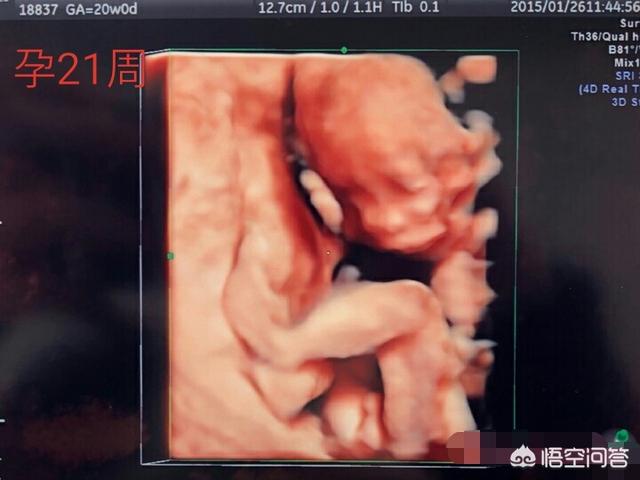

怀孕21周的胎儿图是什么样的(21周B超)

孕21周胎儿身高约20~25cm,体重达到250~350g左右。大概是葡萄柚的大小。

内耳的软骨在这后发育完成,鼻孔打开,B超检查中能清楚看见胎儿的鼻子、嘴巴、眼睑等脸部细节。

21周时,整个孕期已经过半,此时的胎儿面部已经发育的很好了,可以通过B超清晰可见了,但是此时的胎儿身体各项系统以及器官还没有发育完成,这时胎儿身长约25到27厘米左右,此时孕妈妈们任需小心,不可大意。